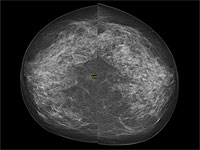

С начала 1990-х годов в Швеции была внедрена программа регулярных маммографических обследований, что позволило снизить уровень смертности от рака молочной железы. Однако, несмотря на доступность скрининга, значительное число женщин не приходит на первичное обследование. Авторы нового исследования решили выяснить, к каким долгосрочным последствиям может привести отказ от первого визита. В исследовании использовались данные шведской программы маммографического скрининга и национальных медицинских реестров. Оно охватило почти 433 тысячи женщин из Стокгольма, за состоянием которых наблюдали с 1991 по 2020 год – в течение 25 лет.

Результаты исследования показали, что 32 % женщин, приглашенных на свое первое маммографическое обследование, не пришли на него. Эти участницы также значительно реже проходили дальнейшие скрининги, что в итоге часто приводило к позднему выявлению заболевания и ухудшению прогноза. У женщин, которые пропустили первое маммографическое обследование, рак молочной железы чаще выявляли на более поздних стадиях. Вероятность обнаружения заболевания на III стадии у них была примерно в 1,5 раза выше, а на IV стадии – в 3,6 раза выше по сравнению с теми, кто прошел первое обследование. В течение 25 лет наблюдений около 1 % женщин, не участвовавших в скрининге, умерли от рака молочной железы, тогда как среди прошедших обследование этот показатель составил 0,7 %. Это соответствует повышенному риску смерти от болезни на 40 %.